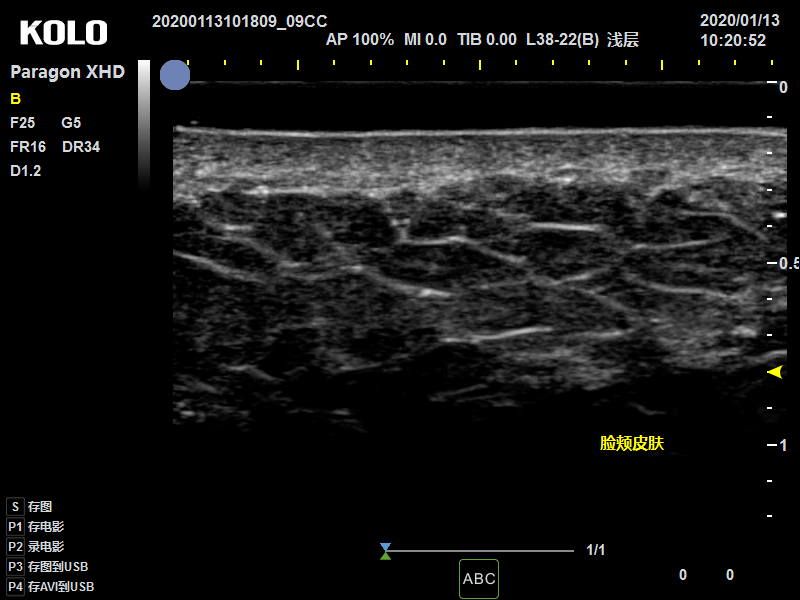

• 正常皮肤层次

皮肤是由表皮、真皮和皮下组织三部分组成的。 超高频皮肤超声可清晰观察皮肤三个基本层次,观察异物进入皮肤层次状态,以及皮肤附属器官毛囊,大汗腺等组织结构。

正常皮肤